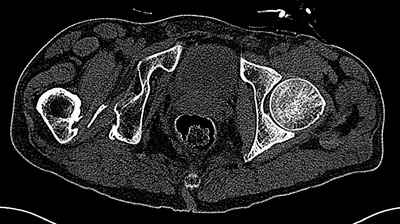

Уважаемые коллеги. Пациент 30 лет 3 года назад в результате травмы получил травматический дефект нижних конечностей до в/3 голеней, был пропущен вывих бедра.

В настоящее время очень неплохо ходит на протезах, движения в неоартрозе близки по объему к здоровой стороне. Основная жалоба - выраженная боль при ходьбе. планируем двухэтапное эндопротезирование - задним доступом мобилизовать проксимальный отдел бедра, резецировать шейку, аппаратом низвести бедро(головку оставить там где она есть, так как больших дефектов не видно(может пригодится в последующем?)). Вторым этапом бесцементное эндопротезирование. Насколько такой вариант реалистичен? Доступ для второго этапа? Может быть другие варианты?С уважением, Максим

На последнем срезе КТ задний край практически отсутсвует по сравнения со здоровой стороной. Разумеется, что это плоскостное изображение, но головка вывихнулась не только в плоскостную щель захваченную на КТ. Если вы считаете, что удастся установить туда чашку даже низкопрофильную, остается пожелать вам успехов. Но перед этим можно смоделировать установку чашки на скиаграммах КТ.

За пожелание успехов - спасибо, думаю это пригодится, не очень понял про плоскостную щель, специально предоставил срезы на уровне свода - он цел, дефект заднего края ниже, за счет заглубления он будет еще меньше, по данным 3d - должно получиться.